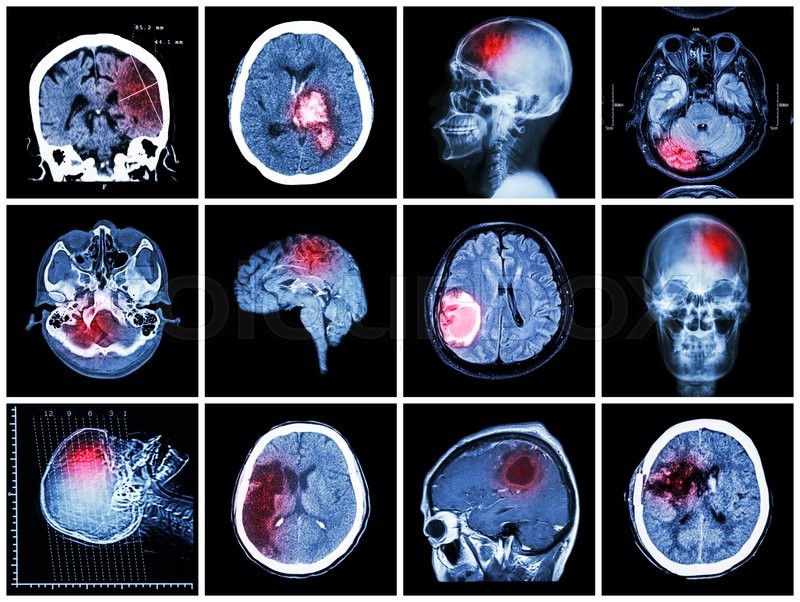

Что видно на полученных снимках

Исследовать можно любые органы и ткани. Снимки играют важную роль в уточнении диагноза и выявлении подозрений. С помощью компьютерной томографии (КТ) и контрастных веществ удается детально рассмотреть изменения в сосудистой системе. Это позволяет выявить ранние стадии опухолей, инсультов, гематом, переломов, смещения костей при травмах, расположение осколков и причины увеличения лимфатических узлов. Технология КТ обеспечивает высокую точность в установлении изменений и их визуализации на экране компьютера.

Разные структуры отображаются в различных цветовых оттенках. Плотные ткани выглядят белыми, так как они поглощают рентгеновские лучи. Мягкие ткани и переломы не создают препятствий для прохождения луча и отображаются на снимках темными пятнами. Процесс получения снимков занимает около 10 минут, и результаты становятся видимыми сразу. Их можно сохранить на цифровом носителе или распечатать. Для получения четкого изображения мягких тканей и жидкости используется контрастное вещество, которое может быть введено, например, в сустав. Это называется артрограммой и необходимо для точного отображения положения иглы в суставе во время дренажа или введения медикаментов.

КТ головного мозга

Процедура занимает около трех минут, а введение контрастного вещества – примерно 20 минут. Специальная подготовка не требуется, и результаты становятся доступны сразу после обследования. Пациент получает последовательные снимки, а также полные изображения всех тканей и образований головного мозга. Информация может быть сохранена в цифровом формате для более детального анализа.

Обследование проводится с целью выявления:

- состояния костной ткани;

- наличия повреждений;

- инородных объектов;

- гематом и кровоизлияний;

- отека мозга после сотрясения;

- нарушений кровообращения;

- абсцессов в мозге.